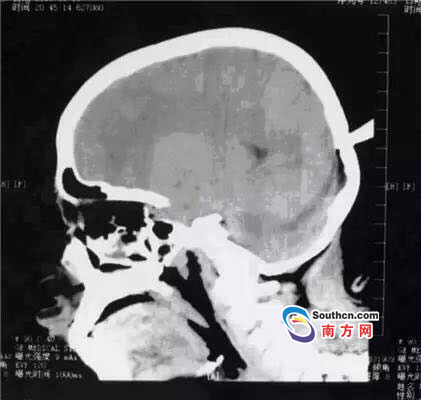

接到小玲受傷的消息,東莞市第三人民醫(yī)院急診科立即啟動了急癥危重患者搶救流程。急癥頭部CT顯示,飛鏢已穿透小玲的顱骨,并突破硬腦膜,情況非常兇險,小玲命懸一線。